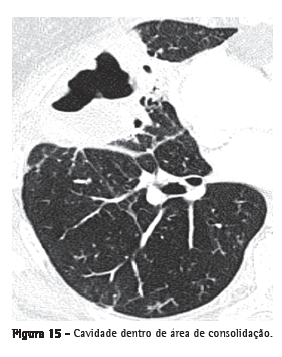

Cavidade (escavação)

Representa espaço que contém gás, com ou sem nível líquido, dentro de um nódulo, massa ou consolidação pulmonar. Geralmente ocorre pela eliminação ou pela drenagem da parte necrótica pela via aérea (Figura 15) ou para o espaço pleural. As paredes costumam ter contornos irregulares e medir mais de 1 mm de espessura. "Cavidade" não é sinônimo de "abscesso". O termo "cavitação" não deve ser usado como sinônimo de "escavação": na língua portuguesa, "cavitação" tem significado diferente, e seu uso é incorreto.(7)